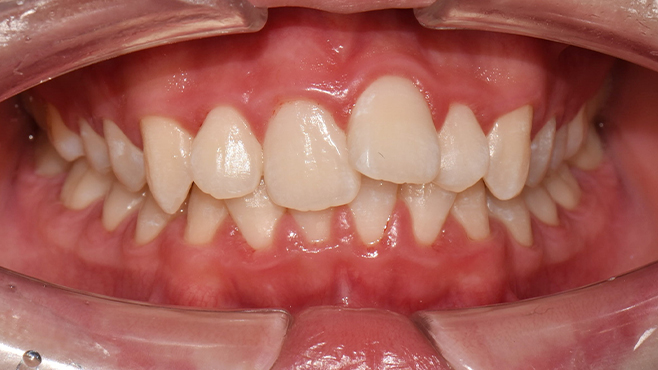

맞는 건 괜찮은데… 충치는 못 참겠습니다|20대 격투기 선수 치과 방문기